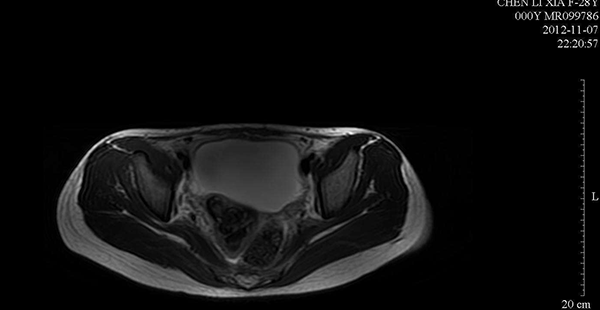

取卵后盆腔积液6.2mm检查图

盆腔积液和腹水是两个不同的东西,盆腔积液是指患者的盆腔内存在积聚性的液体,而腹水是指患者在患有疾病的状态下所导致自身腹腔内游离液体的积聚量超过了正常容量。

盆腔积液具有生理性和病理性两种情况,是取卵后卵巢刺激导致,而腹水属于病理性症状,导致原因有很多,两者的病因、症状以及并发症都是不同的,所以不能混为一谈。